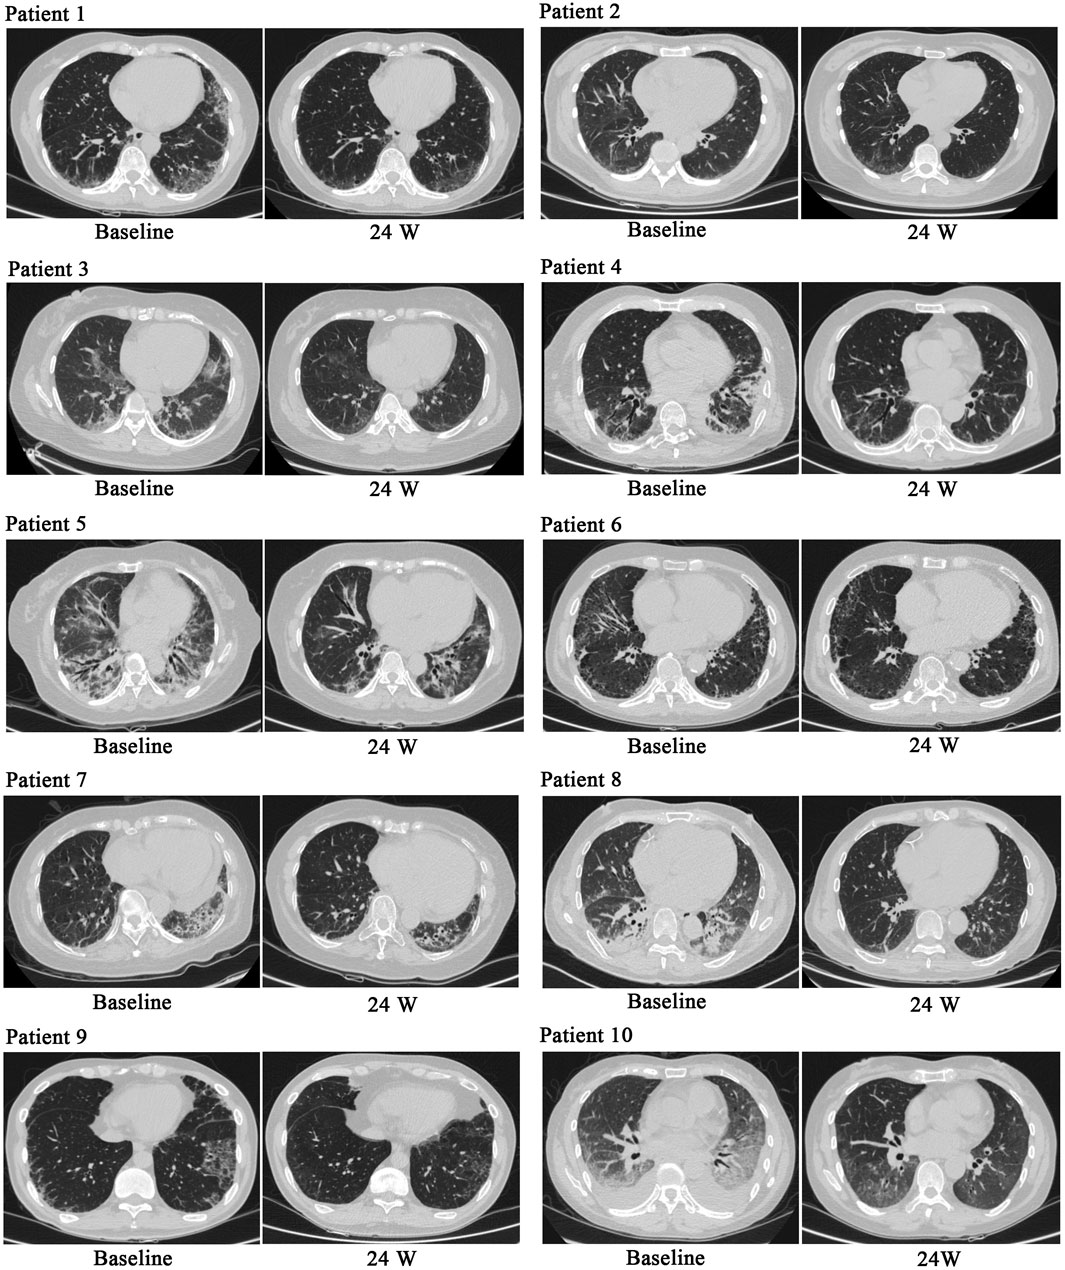

During treatment, all patients were monitored for 24 weeks. Over the course of this treatment, prednisone acetate dosage was gradually reduced to 5–7.5 mg/day, whereas that of telitacicept was increased to 160 mg every 2 weeks. No patient experienced muscle pain, weakness, rash, or joint pain, and all reported considerable relief from dyspnea. Laboratory indicators, including CK, LDH, ALT, AST, ferritin, ESR, and CRP, returned to normal levels (Table 1). The PaO2/FiO2 ratio improved by 28.2% compared with baseline (Figure 1A), whereas the 6MWT outcomes improved by 34% (Figure 1C). In all patients with muscle involvement, the MMT-8 score increased by 25.1% (Figure 1B). All patients’ chest HRCT scans revealed varying degrees of reduction in bilateral lung lesions (Figure 2), and lung function demonstrated considerable improvements (Figure 3); in particular, compared with baseline, FVC% and DLCO% increased by 20.4% and 30.2%, respectively (Figure 4). Only one patient received additional treatment with nintedanib for pulmonary fibrosis due to insufficient improvement in lung function.

Figure 2

CT scans of the lungs from ten patients labeled 1 to 10, each showing baseline and 24-week images. The scans demonstrate variations in lung tissue over time, including changes in density and structure.

Figure 2. Chest HRCT before and after treatment. After treatment, chest HRCT scans demonstrated significant improvements compared with baseline.